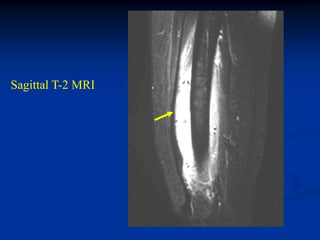

Case #253

29 year male

recent fracture ulna

18 months later

with desmoid tumor

at fracture site

Sagittal T-2 MRI 18 months later with desmoid tumor

Axial T-2 MRI at 18 months